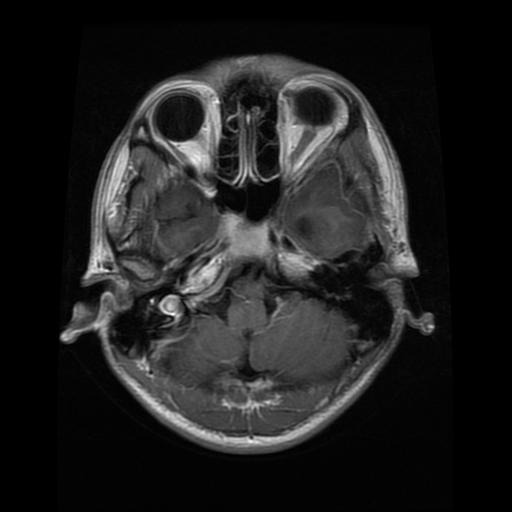

We use the public Brain MRI dataset from Kaggle111https://www.kaggle.com/datasets/masoudnickparvar/brain-tumor-mri-dataset, a widely adopted in the literature for brain-tumor classification. The dataset consists of 2D axial brain MRI slices, provided as raster images with variable spatial resolutions and aspect ratios.

The images were labeled into four categories: no tumor, glioma, meningioma, and pituitary. In the original release, the class counts are no tumor (2000), glioma (1621), meningioma (1645), and pituitary (1757), totaling 7023 images. Table 2 presents the distribution of instances per class along with representative visual examples.

| Class | Quantity | Example |

|---|---|---|

| No Tumor | 2000 | ![]() |

| Glioma | 1621 | ![]() |

| Meningioma | 1645 | ![]() |

| Pituitary | 1757 | ![]() |

| Total | 7023 |